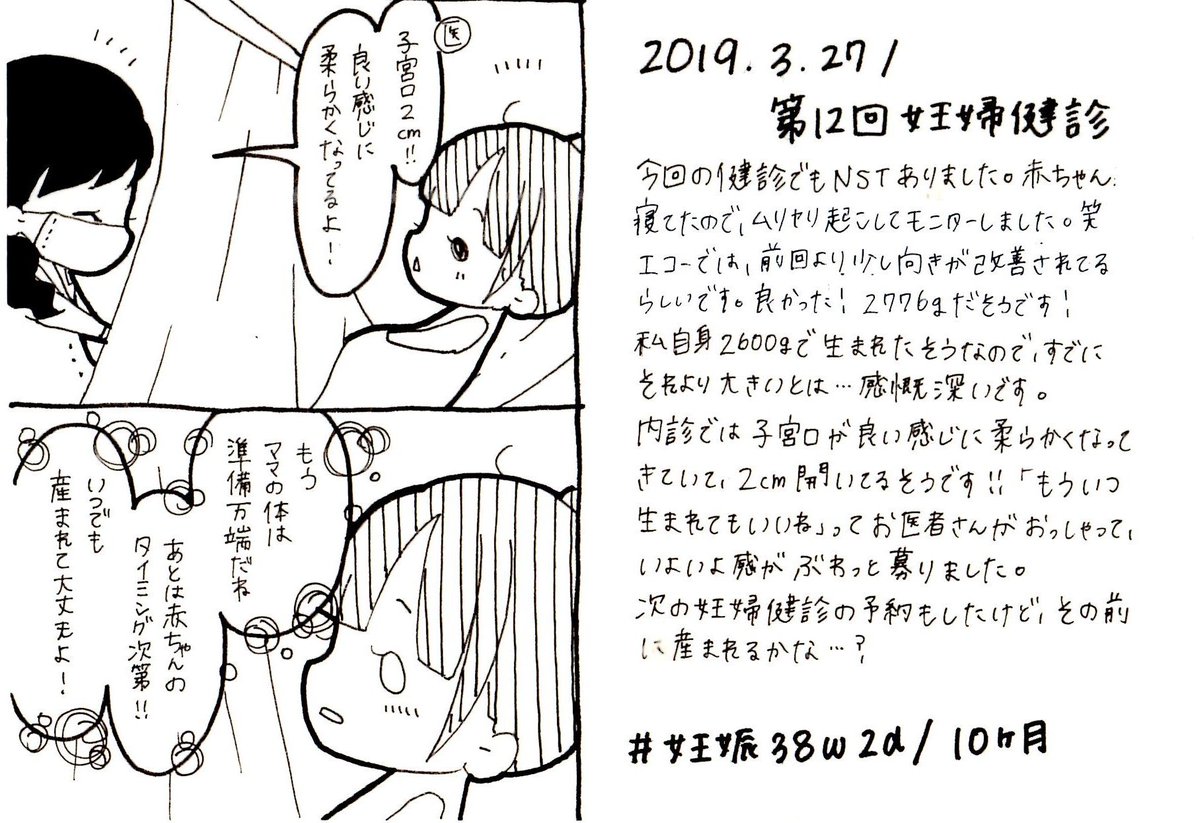

2019.3.27 もう赤ちゃん待ち状態…! お腹もパンッパンです。 エコー載せます、閲覧注意! #育児漫画 #育児日記 #妊娠 #臨月 #妊娠10ヶ月 #正期産 #妊婦健診 #ママ垢さんと繋がりたい #オリジナル漫画 #絵描きさんと繫がりたい pic.twitter.com/RiBXFKKEiP

2019-09-07 10:11:40 拡大

拡大

拡大

拡大